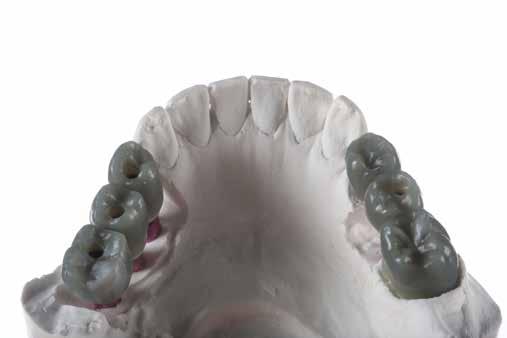

2. ábra: Az okkluzális nézet a fogszerkezet mennyiségét mutatja, a röntgenfelvételen az 1.5. fogon II. osztályú szuvasodás is látható. Még ha lehetséges is ezeket az eseteket koronahosszabbítással kezelni, a végeredmény átlagosan nem kielégítő. A ferrule gyógyulása korlátozott, és olyan parodontális szövődményekkel is találkozunk, mint a fekete háromszögek, a szomszédos fogak gyökérkitettsége. A fogszabályozó extrúzió sokkal előnyösebb.

4. ábra: A fogszerkezet helyreállítása és a fogrestaurációs komplexum ellenálló képességének javítása érdekében ortodontikus extrúziót végeztek a szomszédos fogakra ragasztott drót és egy egyszerű rugalmas ligatúra segítségével.

5. ábra: Az extrudálás nyomon követése néhány hét múlva. Az extrúzió végén a lágyrészek kisebb mértékű újrakontúrozása történt. A szerző általában fibrectomia nélkül végzi az extrúziót, és az extrúzió végén a lágyrészek újrakontúrozását végzi.

6. ábra: A fog az extrúzió és a függőleges preparálás után. A függőleges preparáció a legjobb preparátum a fog szerkezetének megőrzése szempontjából, különösen akkor, ha minimálisan invazív megközelítéssel alkalmazzák. A szerző egy módosított vertikális technikát alkalmaz, amely nagyobb hangsúlyt fektet a pericervikális dentin fenntartására.

7. ábra: A bukkális szerkezet összehasonlítása extrudálás előtt/után . A maradék fogazati struktúra okklusális terhelése most sokkal kedvezőbb a hosszú távú eredmény szempontjából .

8. ábra: Ideiglenes eltávolítás. 9. ábra: Még a szájpadlásfalon is volt fogazati struktúra-gyarapodás. A szájpadlásfal mintegy 35%-a már szilárd fogazati struktúrán van. Ez a jobb biomechanika miatt sokkal jobb eredményt tesz lehetővé a későbbi restauráció számára.

10. ábra: A cirkónium-dioxid korona cementálása üveg-ionomer cementtel . Ezzel a megközelítéssel nyilvánvaló, hogy a ferrule menynyisége a szomszédos fogakra gyakorolt bármilyen komplikáció nélkül nyert. A parodontális apparátus valójában érintetlen. Nincsenek fekete háromszögek, nincs a szomszédos fogak gyökérkitettségének kockázata. Már a szülés napján megvan a papilla, amely kitölti az intraproximális tereket. A nyert ferrule mennyisége hatalmas. A bukkális falon könnyen felismerhetjük, hogy az egész fal már szilárd fogazati struktúrán van, a palatális falon pedig az ajánlott 1-1,5 mm-nél jóval több. A függőleges preparálással szintén könnyen meg tudjuk tartani a visszanyert fogszerkezet mennyiségét , különösen a pericervikális dentin területén, ami a legfontosabb a hosszú távú eredmény szempontjából.